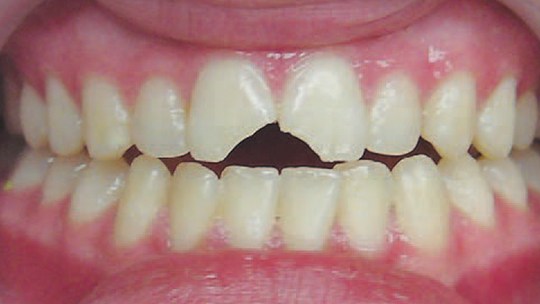

Daimi dişlərin travmatik zədələnmələri uşaq və yeniyetməlik dövründə olan şəxslərdə çox tez-tez rast gəlinir. Tac qırılmaları və lüksasiya travmalar içərisində ən çox rast gəlinənlərdir. Ancaq müxtəlif kliniki hallarda digər zədələnmə formaları da aşkar edilə bilir.

Doğru diaqnostika, müalicə planlaması və sonrakı dönəmdə izləmə uğurlu müalicəyə aparan ən başlıca faktorlardır. Diş travmaları və yaralanmaları tək diş bölgəsini əhatə edən məhdud, eyni zamanda çoxsaylı diş bölgəsini və çənənin alveol darağını əhatə edəcək qədər yayılmış formada rast gəlinə bilir. Çoxsaylı diş zədələnmələrində çox zaman fərqli dişlərdə fərqli növ zədələnmə şəkili aşkar edilə bilir ki, bu da hər bir dişə individual yanaşma və müalicə metodu tələb edir.